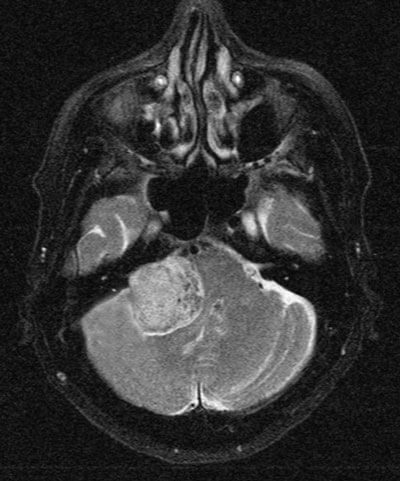

Figure 6: Brain MRI showing a large posterior fossa tumour most likely an acoustic neuroma.

Vestibular schwannomas or acoustic neuromas (Figure 6) are more often seen in the eye clinic for management of postoperative complications than for diagnosis. They usually present to the ENT or neurology clinics because of hearing loss, tinnitus or balance problems. Because these tumours alter the CSF composition or block the fourth ventricle they can also produce papilloedema. Complete surgical removal is seldom achieved and a facial palsy or facial paralysis is a common post operation problem. In addition, because the seventh nerve carries the secreto-motor supply to the lacrimal gland through its greater superficial petrosal branch, a dry eye will ensue.

Thus the vital importance of performing a Schirmer’s test on all patients presenting with a facial palsy cannot be over emphasised, and failure to mention this in an examination viva is a common cause of failure to pass. If the fifth nerve is also involved as may sometimes occur with large acoustics or after operation there is an additional insensitive cornea to be dealt with.